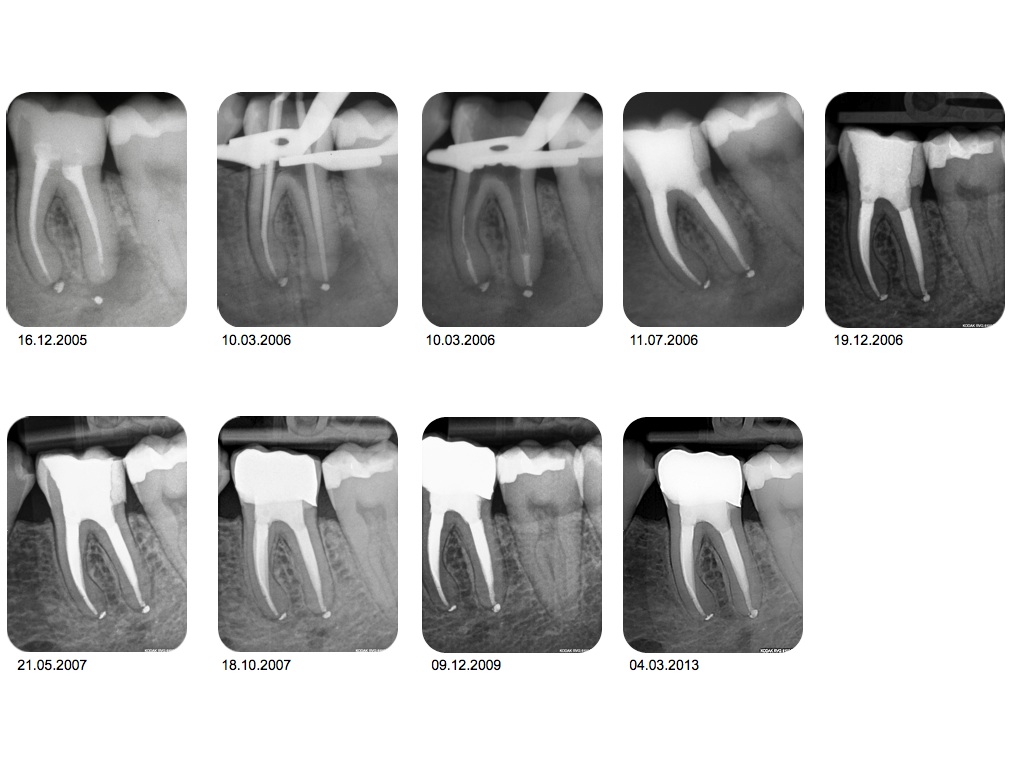

1.002-001